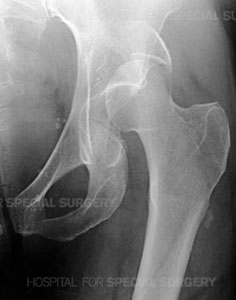

Radiograph of a normal pelvis

The complex nature of these fractures can be better understood by looking at the anatomy that is involved. The pelvis is made up of several bones (ileum, ischium and pubic bones) which create a bony ring, meeting at the pubic symphysis in the front and the sacrum (a bone situated at the lower end of the spine) in the back. Together with a number of ligaments and muscles, the bones of the pelvis support the weight of the upper body and rest on the hip joints. The pelvis protects abdominal organs including the intestines and the bladder, as well as major nerves and blood vessels. Pelvic fractures may occur at any location on the bones depending on the nature of the accident and the areas of impact.